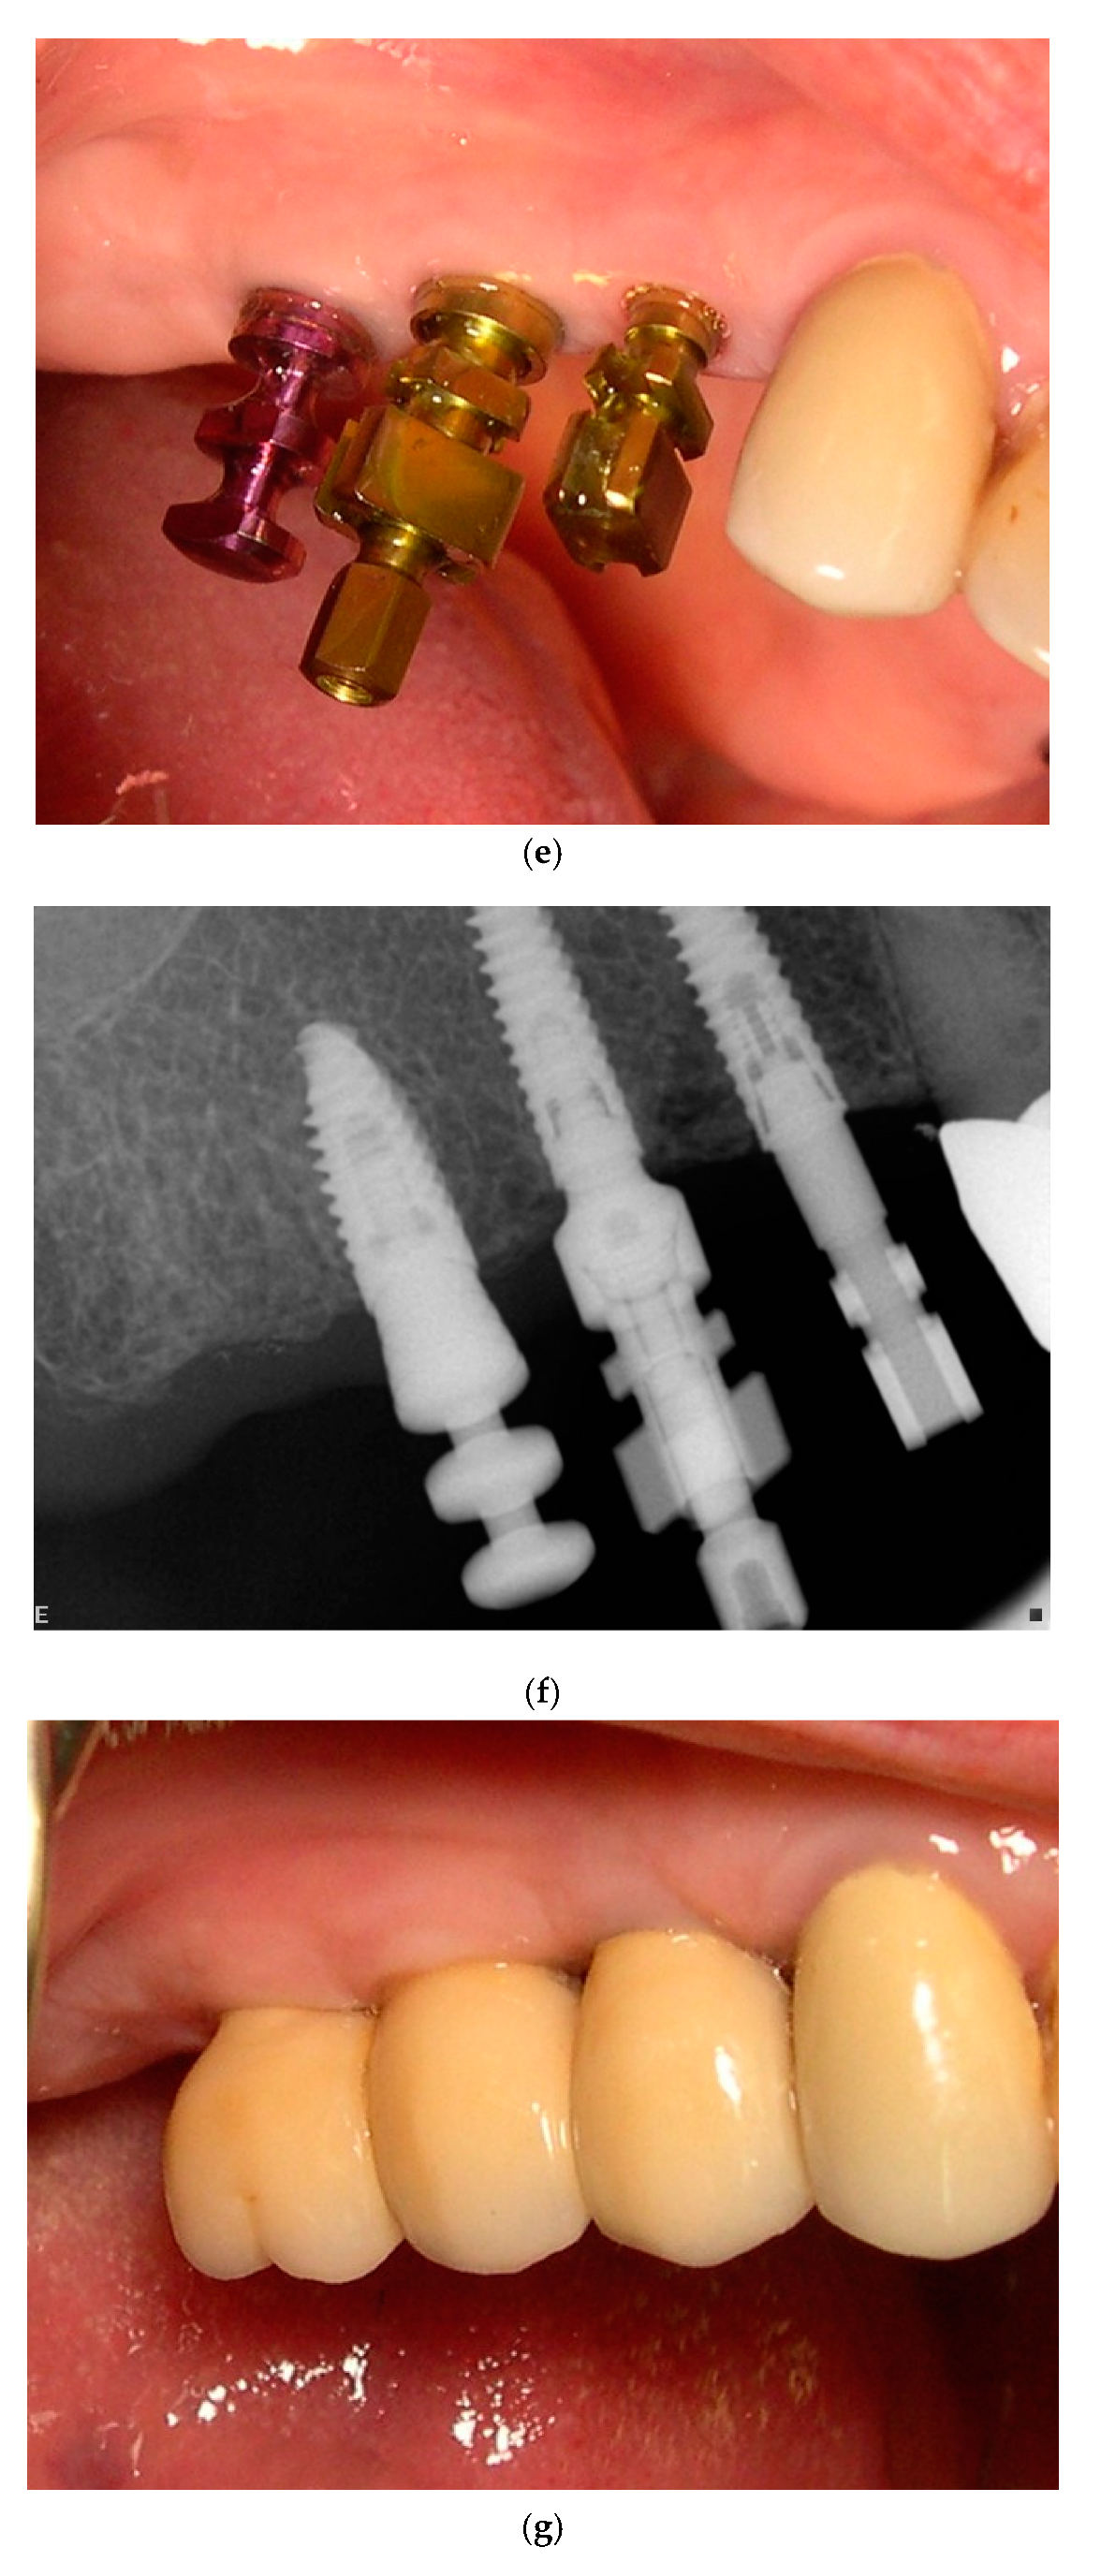

3. Treatment Protocol

3.1. Surgical Technique and Postoperative Management

3.2. Prosthetic Procedures